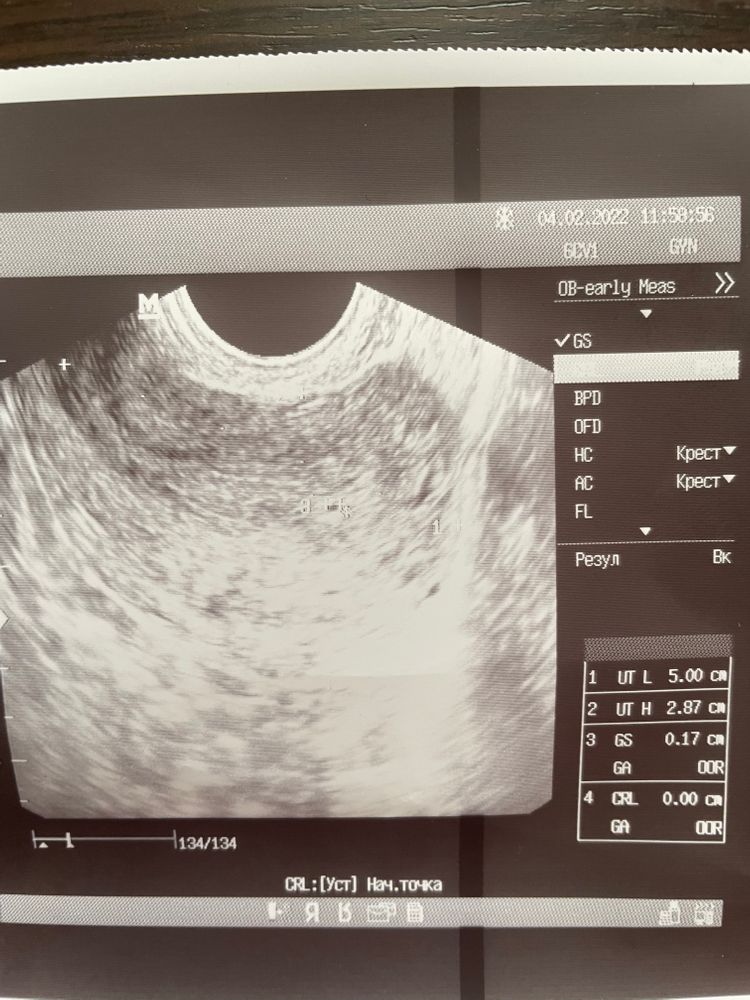

Чашка утреннего кофе, до задержки ещё три дня, на узи сказали очень маленький срок

Чашка утреннего кофе, 4 теста показали слабую вторую полоску

Виктория Чернета, 4 теста разных марок показывают слабую вторую полоску

женя ильчук, на узи можно найти плодное яйцо при значениях хгч от 1000. У вас 1000 по хгч есть?

Изольда Проничка,  Изображение Изображение

Поход на узи Седловидная матка?